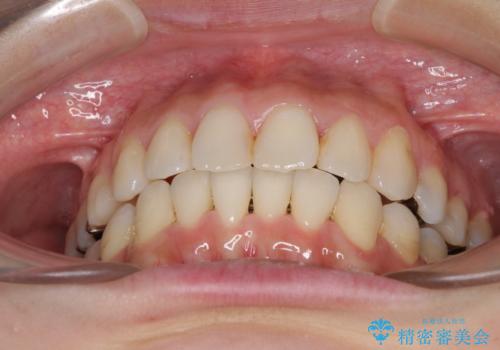

- 上下のデコボコと奥歯の咬みにくさを気にして来院された患者様です。

上顎骨の幅が下顎骨よりも小さいので、拡大装置により骨幅を広げて上下関係を改善し、その後インビザラインにて歯並びを整えることとしました。

上下の骨幅を改善したことで、スムーズに歯列矯正を行うことができました。

矯正治療中に近医で銀歯を外す治療を開始したため、治療後に奥歯の咬み合わせが不十分ですが(こちらは近医での治療により改善するとのこと)、歯列と咬み合わせが改善され、患者様には大変満足していただきました。